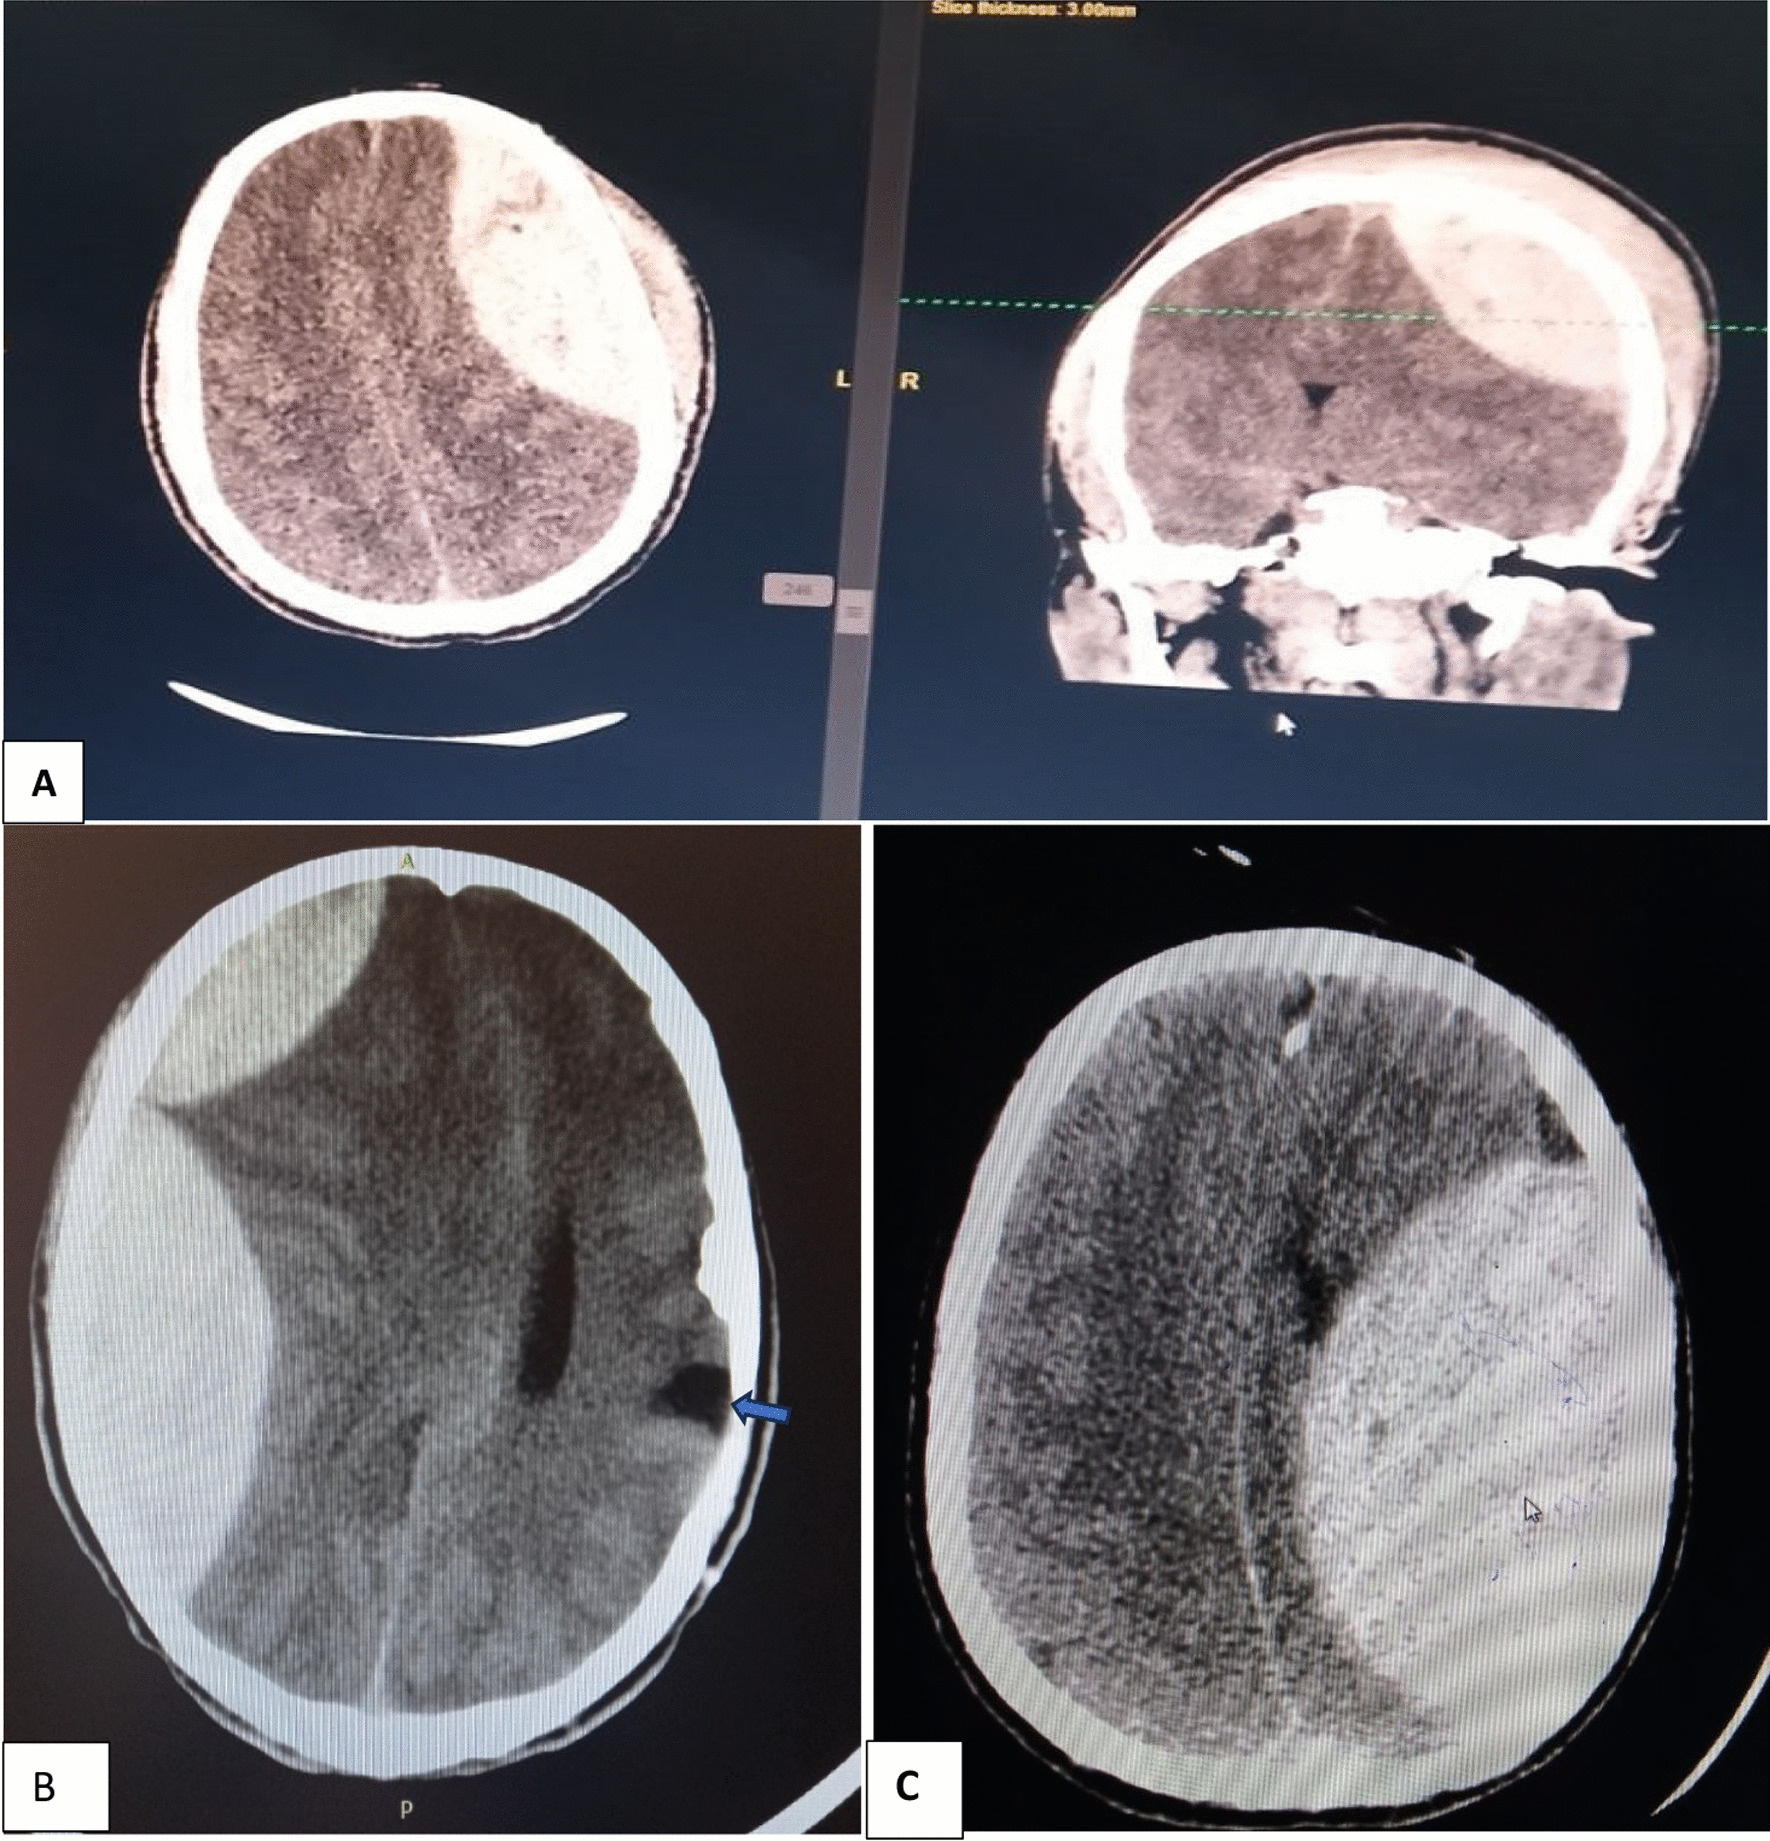

Introduction Intracranial hematoma is the collection of blood in various intracranial spaces. Knowledge of patterns, origins, causes and outcomes of ICH conditions is important for decision-making for urgent surgical interventions such as craniotomy and hematoma evacuations. No prior study was conducted in our setup. Hence, this study aimed to assess the patterns and management outcomes of intracranial hematomas in low-resource setting and tailored our management approach at Jimma University Medical center. Methods An institution-based prospective observational study was conducted at Jimma University Medical Center, Ethiopia, for six consecutive months from June to December 2020. Different data sources and interview methods were used and analyzed using SPSS version 24. A bivariate and multivariate logistic regression was conducted to determine the association between the variables. Results A total of 91 eligible patients were recruited during the study period, with a mean age of 34 years. The majority of patients were males [73 (80.2%)] and more common in reproductive age groups (62.6%), from rural areas (50.5%). About 93.4% of patients reported a history of trauma, and road traffic accidents & fighting account for 63.8% of the trauma cases. Sixty-five percent of patients arrive in the hospital within 24 h. Upon presentation, there were loss of consciousness (48.4%), convulsion (11%), aspiration (9.9%) and increased ICP (12%). The majority (49.5%) of the patients had a mild head injury. The focal neurologic deficits were hemiparesis (29.7%) and hemiplegia (5.5%). Acute epidural hematoma (68.1%) was a common finding, followed by sub-acute subdural hematoma. Of the total study participants, 11% had died. All the surviving patients were accessed at 30 days after discharge and re-assessed, 66 patients had good neurologic recovery (62 upper and 4 lower good recovery), 11 patients had moderate disability (7 lower and 4 upper-moderate disabilities), two patients had a severe disability, and two patients (among those with severe disability) had died. Conclusion Trauma was invariably the cause of intracranial hematoma, and patients with low GCS, papillary abnormalities, aspiration and increased ICP had an increased risk of dying from their illness. It is good to formulate policies to enhance injury prevention and bring about health-oriented behavioral change.

A total of 91 eligible patients were recruited during the study period, with a mean age of 34 years. The majority of patients were males [73 (80.2%)] and more common in reproductive age groups (62.6%), from rural areas (50.5%). About 93.4% of patients reported a history of trauma, and road traffic accidents & fighting account for 63.8% of the trauma cases. Sixty-five percent of patients arrive in the hospital within 24 hours. Upon presentation, there was loss of consciousness (48.4%), convulsion (11%), aspiration (9.9%), and increased ICP (12%). The majority (49.5%) of the patients had a mild head injury. The focal neurologic deficits were hemiparesis (29.7%) and hemiplegia (5.5%). Acute epidural hematoma (68.1%) was a common finding, followed by sub-acute subdural hematoma. Of the total study participants, 11% had died. All the surviving patients were accessed 30 days after discharge and re-assessed, of which 66 patients had good neurologic recovery (62 upper and 4 lower good recovery), 11 patients had moderate disability (7 lower and 4 upper-moderate disabilities), two patients had a severe disability, and two patients (among those with severe disability) had died. Conclusion Trauma was invariably the cause of intracranial hematoma, and patients with low GCS, papillary abnormalities, aspiration, and increased ICP had an increased risk of dying from their illness. It is good to formulate policies to enhance injury prevention and bring about health-oriented behavioral change.